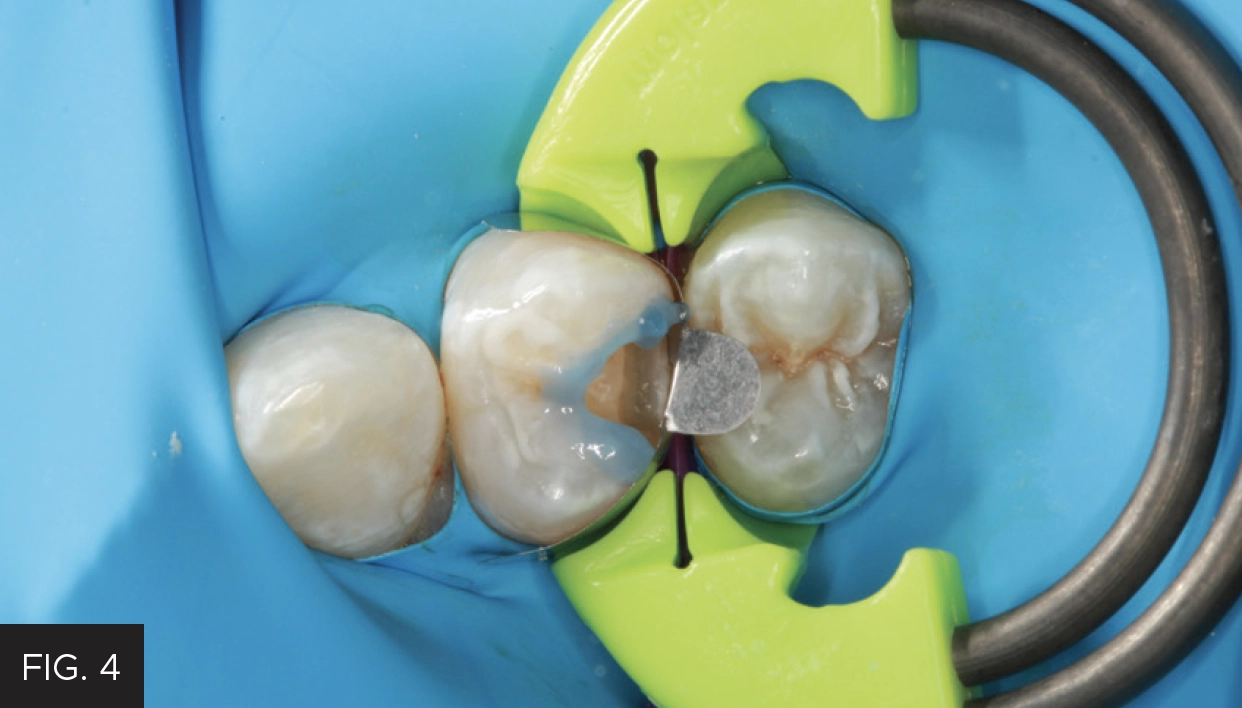

The selective-etch technique was used, etching only the enamel surfaces with 35% phosphoric acid etch for 15 seconds. (FIG. 4) The tooth was then rinsed and dried. Adhesive (Adhese® Universal VivaPen®, Ivoclar) was then placed and agitated on the dentin and enamel surfaces for 20 seconds, dried with air, and light-cured with a high-performance LED polymerization light (Bluephase, Ivoclar) for 20 seconds.

The selective-etch technique was used prior to placement of the adhesive to maximize the bond strengths while minimizing any risk of post-op sensitivity.